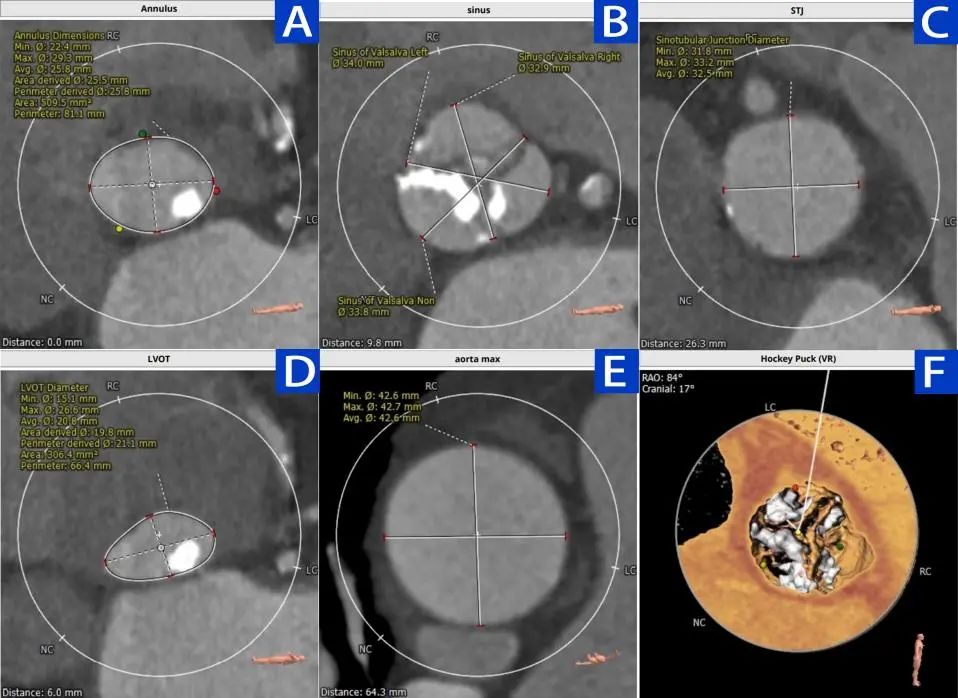

2.术前瓣膜CT测量:A .瓣环测量; B.瓦氏窦测量;C.窦管交接区测量;D.左室流出道测量;E.升主动脉(最宽处)测量;F.虚拟瓣叶形态,钙化分布。

3.主动脉根部多平面测量

3.1 瓣上2mm

3.2瓣上4mm

3.3瓣上6mm

3.4瓣上8mm

4 心脏角度 约68°,呈横位+升主扩张

患者为三叶瓣,瓣叶增厚,极重度钙化,左冠窦可见柱状钙化延申至流出道,双冠脉风险高度尚可,瓣叶未见冗长,考虑冠脉风险较低,心脏角度约68°,呈横位+升主扩张,预备上Snare;收缩期左室测值较小且流出道短径约16.8mm,选择20球囊预扩,预装L26 Venus-A瓣膜。